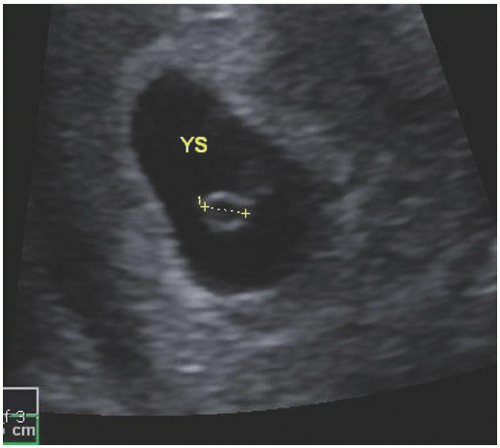

Yolk Sac Ultrasound

yolk sac ultrasound